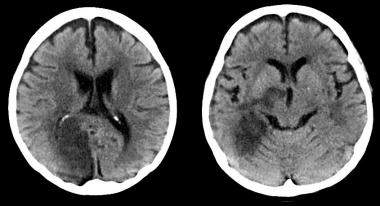

ACV isquémico pequeño: ¿demasiado bueno para tratarlo?

29 septiembre 2016

Según un estudio observacional, los pacientes con ictus isquémico y lesiones pequeñas en la tomografía computarizada de perfusión podrían no beneficiarse con la trombolisis. Annals of Neurology, agosto de 2016